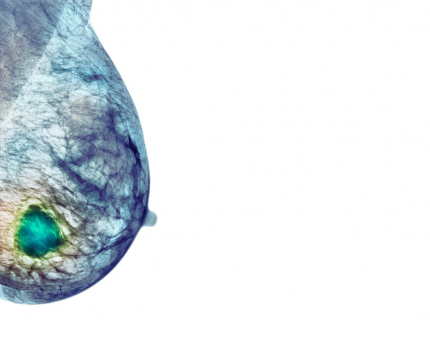

Le cancer du sein

Cliché de mammographie mis en couleur

Le développement du cancer du sein est un processus à long terme et très complexe. En général, le développement de la lésion cancéreuse est précédé de la formation d’une lésion non invasive [50]. En fonction de plusieurs facteurs intrinsèques et extrinsèques, cette lésion non invasive peut évoluer vers une forme invasive [51-52]. Il est donc crucial de comprendre cette transition d'une forme localisée à une forme invasive. À cet égard, Choi et al. ont décrit un modèle microfluidique [50] composé de deux chambres de culture superposées (Figure 7) simulant la lumière du canal et le capillaire vasculaire stromal, séparés par une fine membrane. Ce modèle microfluidique a ensuite été utilisé pour évaluer l'efficacité et la toxicité d'un médicament anticancéreux (Paclitaxel) (Figure 6) qui a été injecté dans la chambre inférieure (capillaire) pour imiter l'administration intraveineuse.